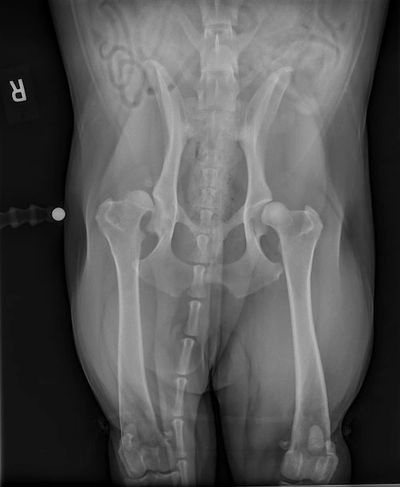

KALÇA DİSPLAZİSİ

Daha çok büyük ırk köpeklerin sorunudur. Kalça eklemi bağları gevşekliği ile eklem yüzeyleri birbirine sürtünmesi ile ses, aşınma, topallık, anormal hareket, güç kaybı, merdiven çıkmakta zorlanma, ağrı gibi belirtiler meydana gelir. Operatif tedavi yöntemleri ve semptomları azaltmaya yönelik medikal tedaviler uygulanabilir. Derhal Veteriner Hekiminize danışın !